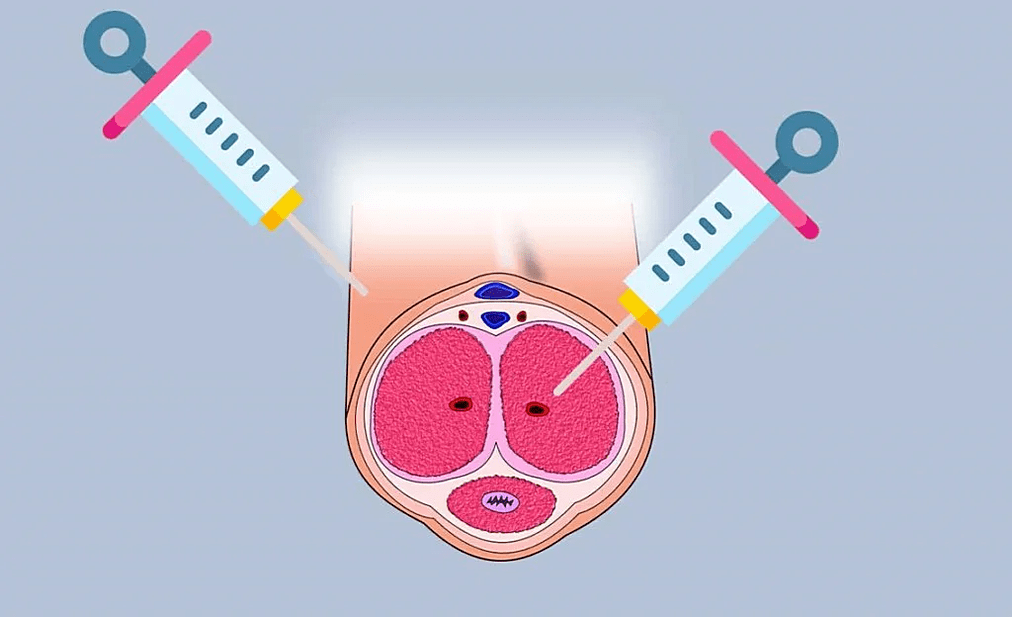

Insertion of the filler into the penis occurs in several stages:

- The groin area is treated with an antiseptic and covered with a disposable sterile diaper.

- An anesthetic gel is applied to the penis, which takes effect after 15 minutes.

- The required amount of hyaluronic acid drug is drawn into the syringe. A thin needle is inserted into the subcutaneous layer and the filler is slowly injected. The doctor ensures that the hyaluronate is distributed evenly in the injection area.

- An aseptic bandage and patches are applied to the injection site.

The duration of the procedure depends on the number of injections and lasts from half an hour to an hour, taking into account the time of anesthesia in the places for the introduction of hyaluronic acid.

Methods of administration

There are several methods of inserting the filler into the head of the penis. The doctor chooses the technique according to the indications. More often, several methods are combined to improve the aesthetics of the head of the penis:

- Fan method— Hyaluronate is injected with a thin needle in different directions through a fan-type puncture.

- Point method- the injection is performed in a limited part of the penis to eliminate irregularities or deformations.

- Outline presentationThe filler is applied along the crown of the head, after which the contour becomes voluminous and more pronounced.